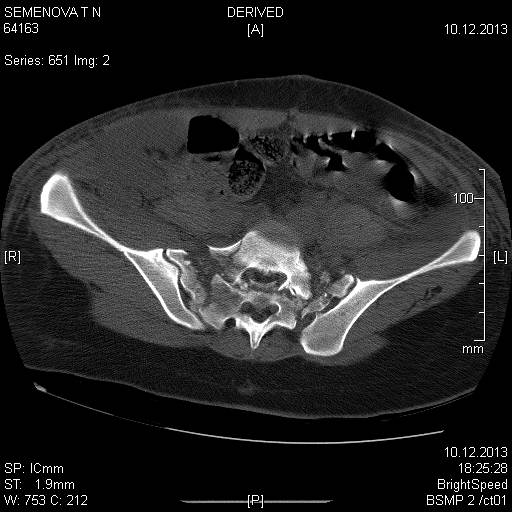

Доброго времени суток коллеги! Прошу вас подсказать тактику в решении оперативного лечения следующего сложного повреждения таза. Был ли опыт в фиксации подобных повреждений? Травма 03.12.2013,больная переведена из лечебного учреждения соседней области.На данный момент у больной следующий диагноз: ЗЧМТ,сотрясение головного мозга;Закр. травма грудной клетки,множественные переломы ребер справа с повреждением ткани легкого,правосторонний гемопневмоторакс,состояние после торакоцентеза;Закр.травма живота,разрыв селезенки,гемоперионеум, состояние после лапаротомиии спленэктомии;Закр. оскольчатый перелом сред-верх\3 левой бедренной кости, состояние после накостного металлостеосинтеза; Закр.поперечный переломовывих на уровне S1S2, многооскольчатый перелом латеральных масс крестца с обеих сторон,перелом обеих лонных и седалищных костей. Перелом поперечных отростков L1,L2,L3,L4, L5 позвонка. ШОК 3ст. Вкратце изложил диагноз. В настоящее время состояние больной тяжелое. Первым этапом планируем наложить АНФ (переднюю раму) После стабилизации состояния необходимо будет выполнить фиксацию: . Имеется один вопрос - какие импланты необходимы т.е. в какой комбинации и какая последовательность фиксации?

Добрый день! Станислав! Повреждение таза действительно тяжелое. В данном случае по мимо перелома передних колонн, что не самое страшное, имеется H-образный перелом крестца со смещением каудальной части. перелом поперечных отростков подтверждает вертикально нестабильный характер травмы таза. Предложенная конструкция действительно является вариантом решения проблемы,а скомпоновать ее можно из любого транспедикулярного фиксатора той фирмы которая работает у вас с нейрохирургами.Но помимо этого необходимо выполнить декомпрессию корешков конского хвоста. в противном случае та неврология которая есть и сейчас останется на всю жизнь. Судя по тяжести состояния к лечению перелома крестца сможете приступить не скоро, скорее всего на данный момент доминирует легочный дисстресс синдром, наверняка есть анемия после гемопневмоторакса, лапаротомии и накостного остеосинтеза бедренной кости.Поэтому когда дойдет дело до крестца репонировать отломки будет весьма сложно. Мы бы начали с остеосинтеза ребер, чтобы сделать пациента мобильным, передние колонны можно фиксировать перкутанно винтами, сзади кроме илиолюмбальной конструкции, ляминэктомия с целью декомпрессии, репозиция и дополнительная фиксация реконструктивными пластинами, лучше LCP. Пригласите на операцию нейрохирурга-вертебролога. Успехов.

В данном случае кроме фиксации крестца требуется декомпрессия канала. А вправленный вывих надо удержать, и вертикальные пластины с юникортикальной возможностью в 2.7 мм помогут создать стабильность. Кроме этого, надо создать условия по предупреждению компрессии крестца с двух сторон. В связи с тем, что процедура заканчивается в области крестца, а также наличие повреждения позвонков, это ограничивает возможности педикулярной фиксации. Мне кажется, от боковой компрессии лучше удержала бы согнутая по контуру крыла узкая в 4.5 мм балка-пластина.